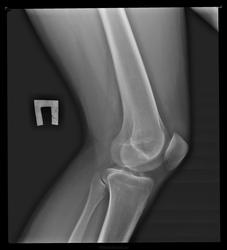

Парень, 17 лет, болезнееность при ходьбе в обоих суставах.

Костных изм. не видно.

По снимкам норма.

Артроза нет.

Рентгенологических данных за ДОА нет.

Для уточнения диагноза полезно сделать УЗИ коленных суставов.

ИНФОРМАТИВНОСТЬ УЗИ очень низкая.сделайте МРТ. хотя если болят оба сустава,то можно и к ревматологам сходить(ревмо-фактор,АСЛО и т.д.) а на R ничего не видно.нужен тщательный анамнез